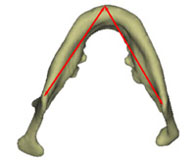

3차원 입체영상의 활용은 여러 가지 방향으로 가능한 반면 저자의 경우에는 안면비대칭 환자에서 “어느 구조물의 좌우 차이가 이부편위(chin deviation)를 야기하였는가”의 파악에 3차원 입체영상이 필요하였으며 이의 사용결과 2차원사진으로는 알 수 없었던 여러 가지를 이해할 수 있게 되었다. 얼핏 생각하면 이부편위는 좌우 ramus의 길이 차이 때문에 나타난다고 이해할 수 있다. 그러나 ramus 길이 뿐 아니라 mandibular body 길이차이에 의해서도 이부편위는 나타날 수 있고 이러한 부위별 파악은 특히 수술계획 수립에 매우 중요하다. 또한 어떤 환자에서는 ramus의 길이나 body의 길이는 좌우가 비슷한데, 정면에서 보았을 때 또는 측면에서 보았을 때 ramus의 경사도 차이로 인해 이부편위가 나타난 것을 발견할 수 있었다. 이러한 ramus 경사도 차이는 측모두부방사선사진이나 정모두부방사선사진에서도 관찰될 수 있지만 2차원적 사진의 경우 projection error로 인해 평가에 확신을 할 수 없는 반면 3차원 입체영상의 경우에는 이미지를자유자재로 돌려볼 수 있으므로 보다 용이하게 그리고 정확하게 이해를 할수 있었다. 3차원 입체영상을 통하여 외관상 보이는 이부편위의 원인을 살펴본 결과 저자는 (1)상악고경의 좌우차이 (2)ramus 길이의 좌우차이 (3)전방에서 보았을 때 좌우 ramus inclination의 차이 (4)측방에서 보았을 때 좌우 ramus inclination의 차이 (5)mandibular body 길이의  좌우차이 (6)mandibular body 윤곽의 좌우차이 등 6가지가 이부편위에 기여함을 발견할 수 있었다 (그림5).

그림 5. 이부편위에 기여하는 요인들. 이부편위는 단순히 ramus의 좌우차이에 의해서만 나타나는 것은 아니다. 3차원이미지를 자세히 관찰해 보면 상기 6가지 부위에서의 좌우차이가 환자로 하여금 "턱이 돌아갔다"고 느끼게 하고 있음을 알 수 있다. a. maxillary height; b. ramus length; c. frontal ramal inclination; d. lateral ramal inclination; e. body length; f. body height.